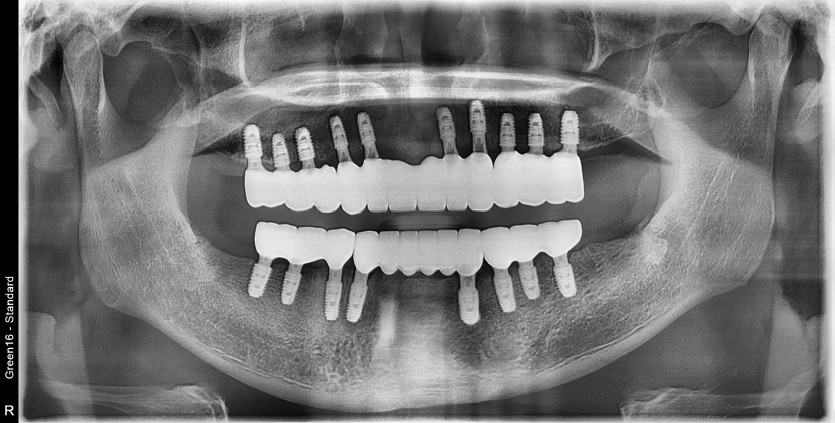

전체 임플란트 증례입니다.

18개의 임플란트로 완성하였습니다.